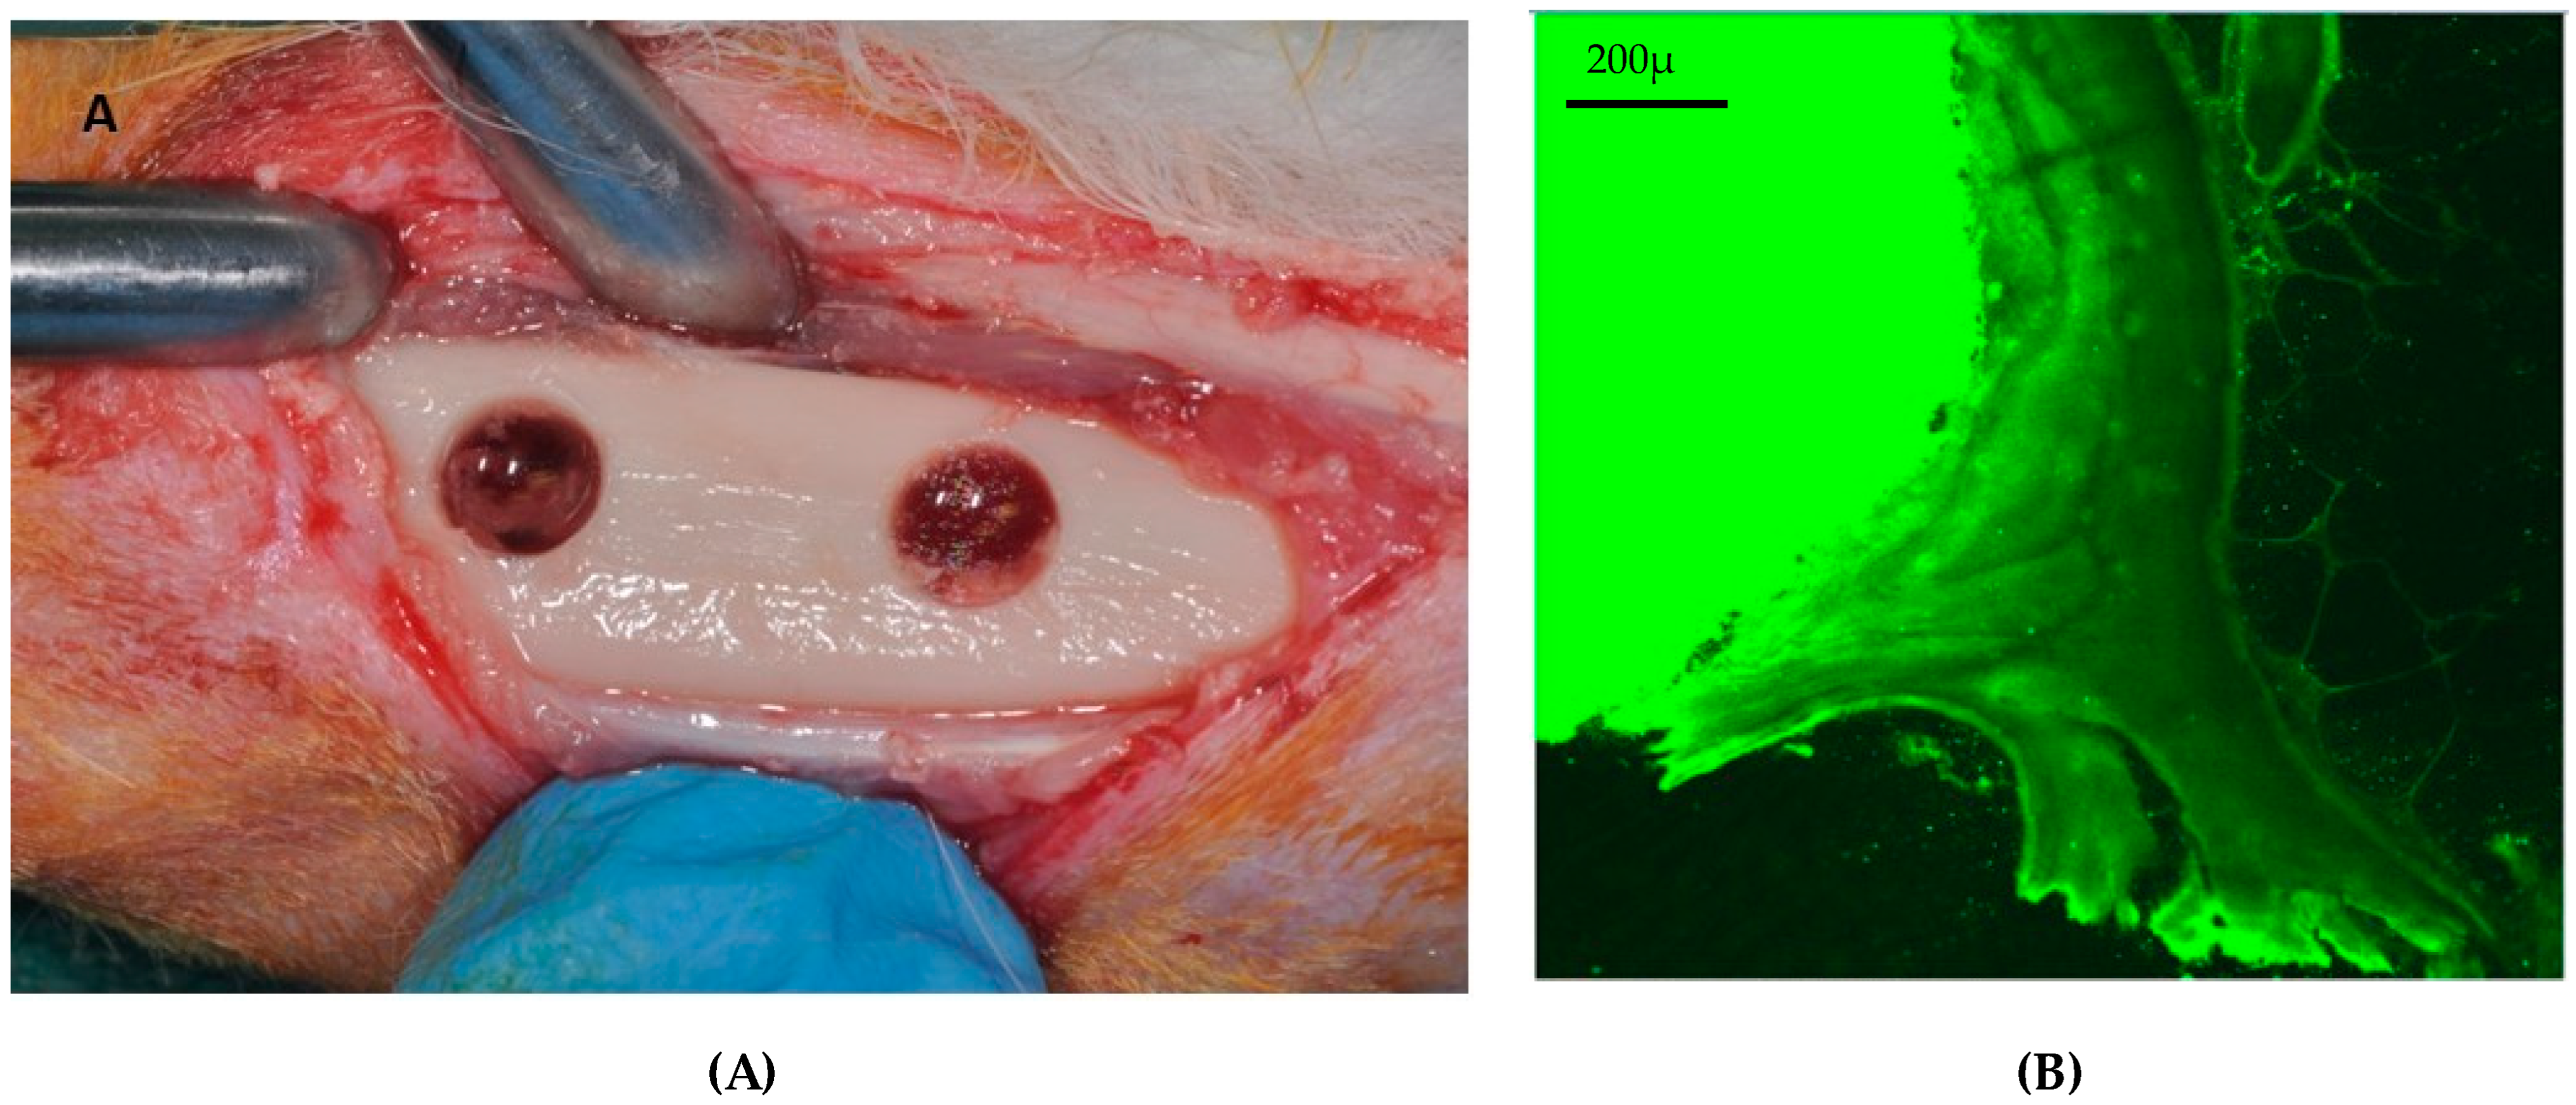

4.1. Sheep

- Ferguson, J.C.; Tangl, S.; Barnewitz, D.; Genzel, A.; Heimel, P.; Hruschka, V.; Redl, H.; Nau, T. A Large Animal Model for Standardized Testing of Bone Regeneration Strategies. BMC Vet. Res. 2018, 14, 330. [Google Scholar] [CrossRef] [PubMed]

- Pobloth, A.-M.; Johnson, K.A.; Schell, H.; Kolarczik, N.; Wulsten, D.; Duda, G.N.; Schmidt-Bleek, K. Establishment of a Preclinical Ovine Screening Model for the Investigation of Bone Tissue Engineering Strategies in Cancellous and Cortical Bone Defects. BMC Musculoskelet. Disord. 2016, 17, 111. [Google Scholar] [CrossRef]

- Scarano, A.; Lorusso, F.; Ravera, L.; Mortellaro, C.; Piattelli, A. Bone Regeneration in Iliac Crestal Defects: An Experimental Study on Sheep. BioMed Res. Int. 2016, 2016, 4086870. [Google Scholar] [CrossRef]

- Parra, M.; Benalcázar Jalkh, E.B.; Tovar, N.; Torroni, A.; Badalov, R.M.; Bonfante, E.A.; Nayak, V.; Castellano, A.; Coelho, P.G.; Witek, L. The Influence of Surface Treatment on Osseointegration of Endosteal Implants Presenting Decompressing Vertical Chambers: An In Vivo Study in Sheep. Int. J. Oral Maxillofac. Implants 2022, 37, 929–936. [Google Scholar] [CrossRef]